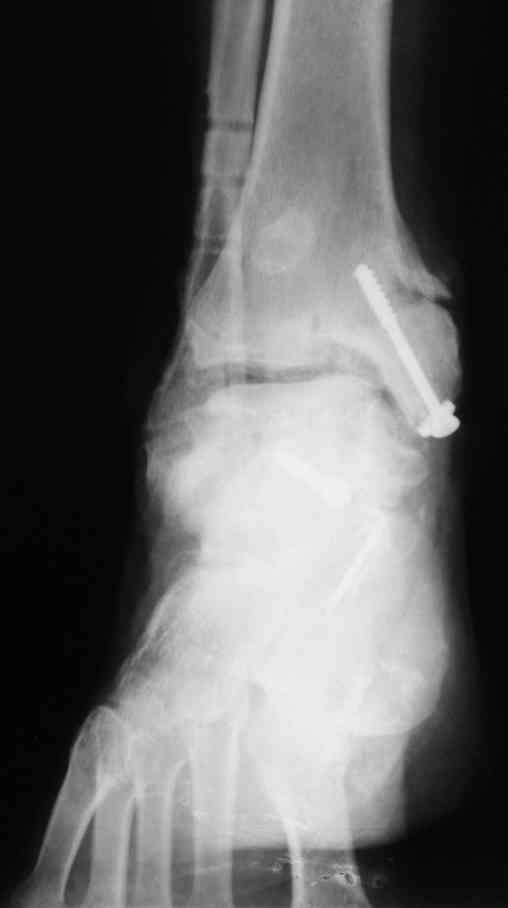

Решили не связываться с остеосинтезом, а сделать сразу берцово-пяточный блок. Снимки в приложении.

По завершении удлинения, наверно, заштифтуем.

Комментарии/критика приветствуются.